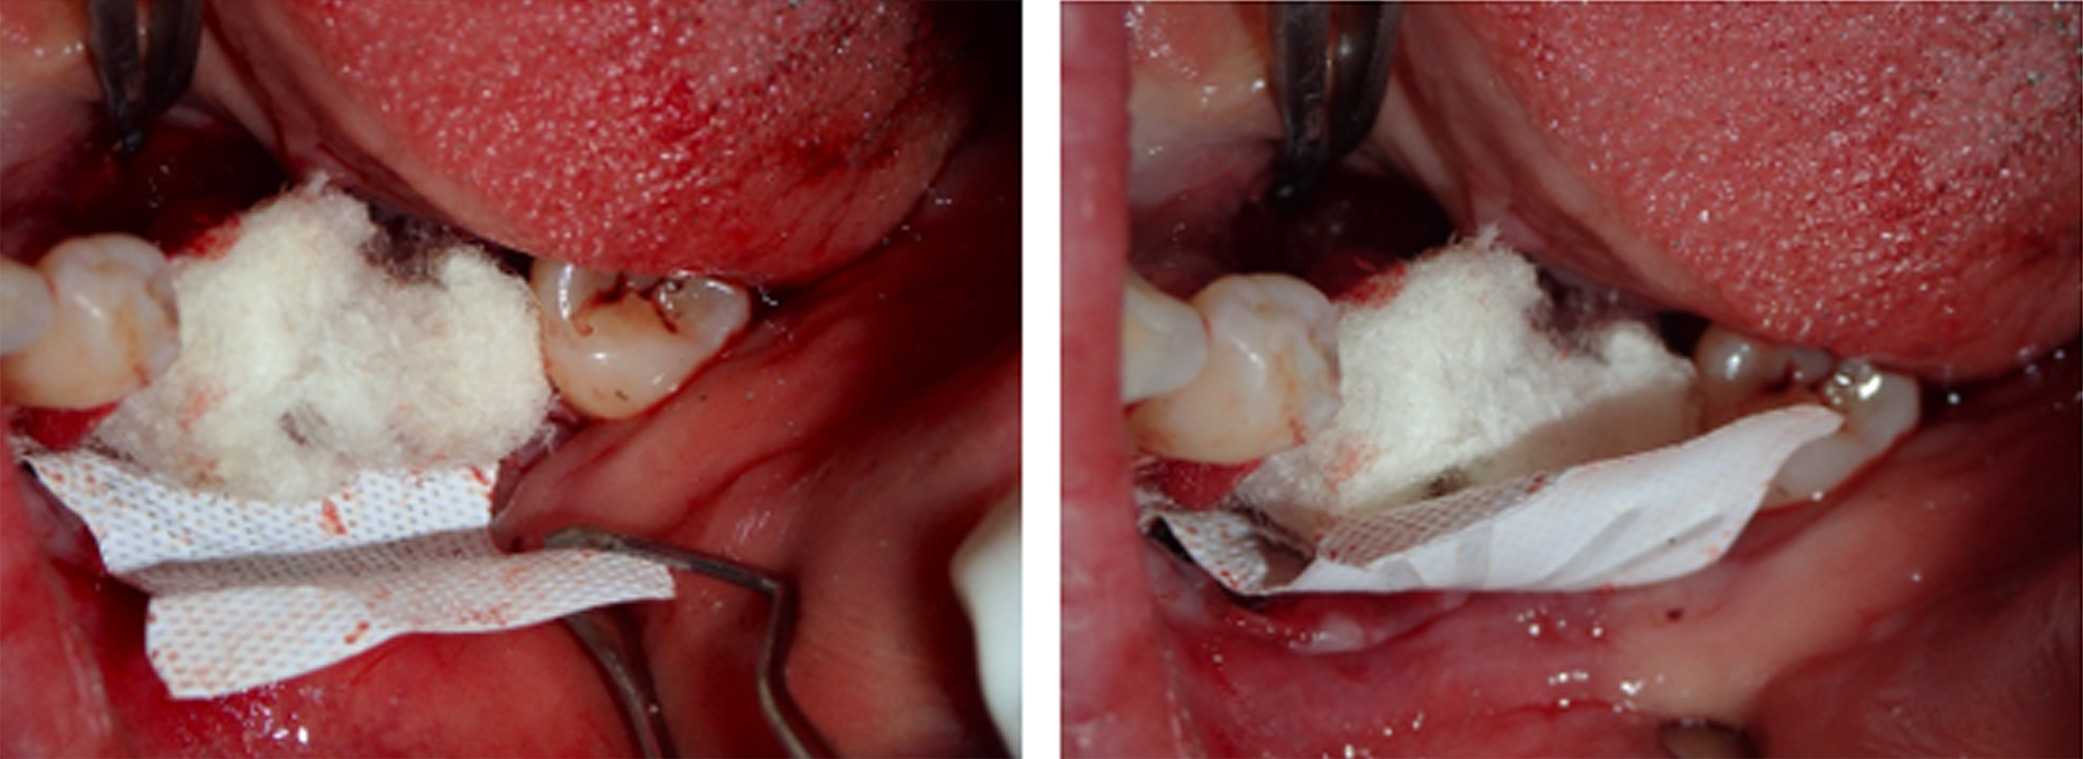

Next, buccal and lingual reaming was carried out to ensure bleeding and adequate irrigation of the bone graft (Figure 5). GBR was facilitated first through a combination of autograft obtained from the mandibular ramus using a SafeScraper® (META; Reggio Emilia, Italy) and C/C Mix (Figure 6). Then, an outer layer of F-DBM was added for extra volume and to contain the underlying particulate (Figure 7). To maintain stability of the bone graft, a Cytoplast dense titanium-reinforced PTFE membrane (Osteogenics; Lubbock TX, USA) was fixed with buccal and lingual pins (Figure 8). Finally, an outer layer of bovine pericardial membrane (Nobel Biocare, Kloten, Switzerland) was placed to provide a bilayer of interlaced, multidirectional Type 1 collagen fibers (Figure 9). A combination of horizontal mattress and simple sutures with nonresorbable Cytoplast PTFE 3.0 monofilament (Osteogenics) were then used to provide optimal closure of the flap without tension. Perioperative computed tomography (CT) scans confirmed pin and titanium-reinforced placement but, characteristic of regenerative materials, bone particulate and fibers were not radiopaque (Figure 10).

Figure 6. Guided bone regeneration was first facilitated through a combination of C/C Mix and autograft obtained from the mandibular ramus

Figure 7. An outer layer of F-DBM was added for extra volume and to contain the underlying particulate